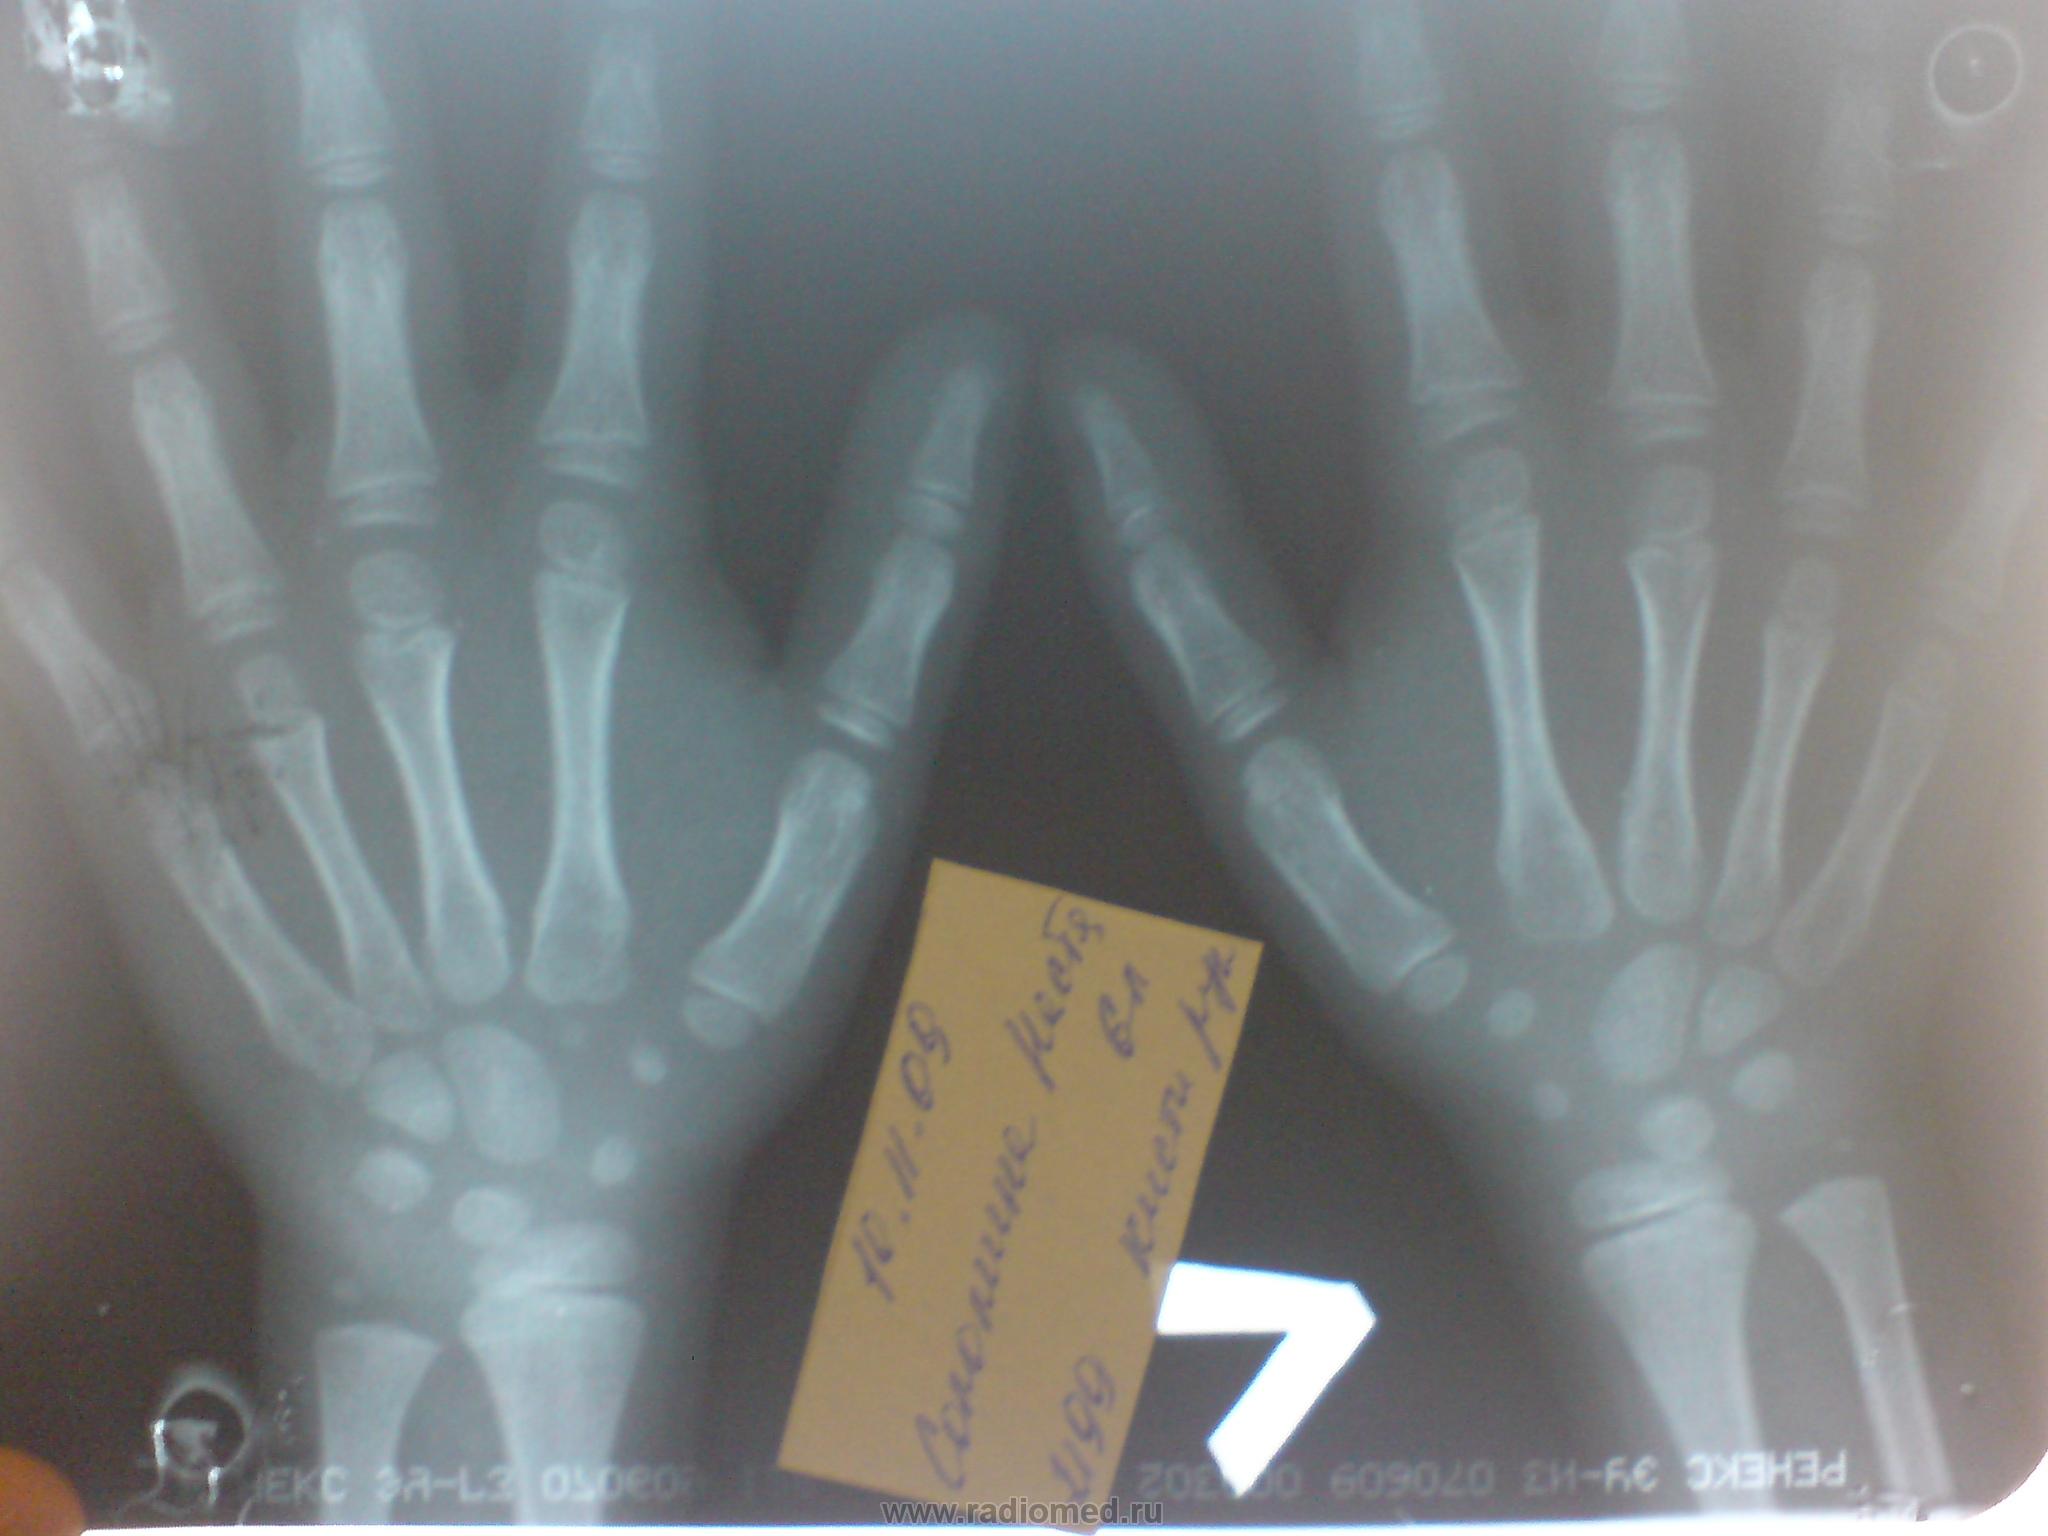

Что-то никак не могу определиться с костным возрастом. Паспортный возраст 6 лет. Уважаемые коллеги прошу помощи. И, если возможно, поделитесь информацией по-поводу методики определения костного возраста.

Порядок появления точек окостенения  следующий: на 1-м году - головчатая и крючковидная кости, на 2-3-м - трехгранная кость, на 3-4-м - полулунная, на 4-6-м - кость-трапеция и трапециевидная, на 5-6-м - ладьевидная. У девочек все точки окостенения закладываются на один год раньше, чем у мальчиков. Окостенение гороховидной кости происходит у девочек в 7-8 лет, у мальчиков в 10-11 лет

В данном случае костный возраст соответствует паспортному. Rg-Doс, куда вам сбросить книжку по костному возрасту?